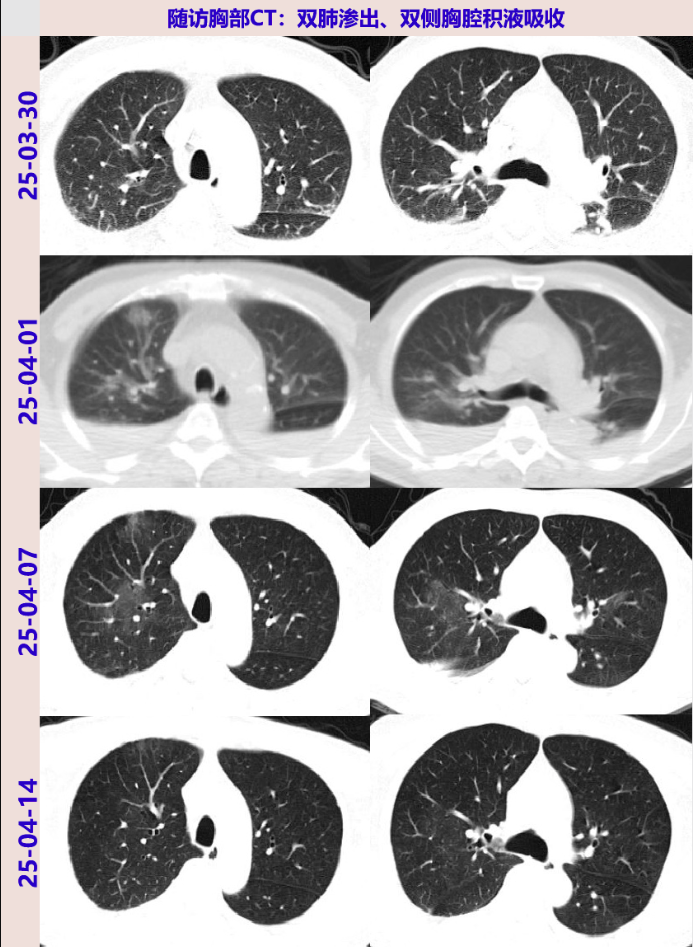

2025-04-03 完善骨髓穿刺活检,术后予甲泼尼龙40mg qd ivgtt,体温降至正常3天。

2025-04-07 再次发热,Tmax 38℃,复查胸部CT示两肺炎症较04-01PET/CT有吸收;骨髓初步病理:造血组织中可见到较多肉芽肿样病变,肉芽肿结节内未见到凝固性坏死,HE切片中淋巴细胞、浆细胞数目不增多;骨髓涂片:骨髓增生活跃,髓象中粒系增生明显活跃伴核左移,片中浆细胞略易见,分类占2.5%,形态无殊。

2025-04-11 布氏杆菌抗体、寄生虫抗体回报阴性。患者仍反复发热,与血液科沟通后04-11起予甲泼尼龙40mg qd ivgtt抗炎,治疗后体温热峰下降,无明显咳嗽、气促。

2025-04-14 体温再次升高,Tmax:38.4℃;复查胸部CT:两肺炎症渗出,两侧少量胸腔积液伴两肺不张,均较前25-04-07片有所吸收,再次与血液科沟通后拟至血液科抗肿瘤治疗。

患者胸部CT示双肺多发渗出、双侧胸腔积液,病灶短期增多,伴BNP升高、低蛋白血症,多次痰病原学阴性,经利尿、补充白蛋白治疗后BNP、Alb恢复正常,短期随访胸部CT双肺渗出及胸腔积液吸收,故考虑心功能不全、低蛋白血症所致肺水肿、胸腔积液。